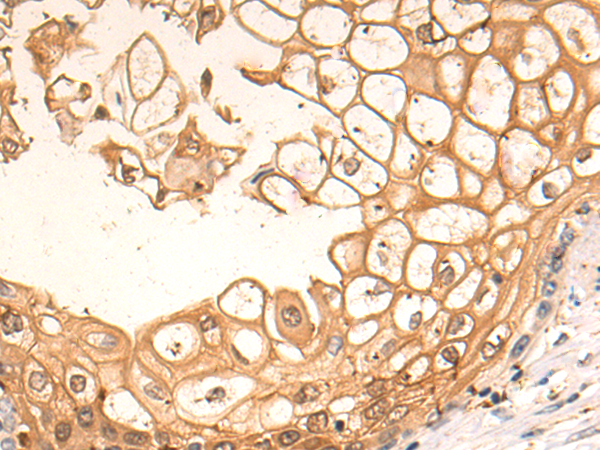

ELISA, IHC

LSAMP

IHC positive control:

Human brain

IHC Recommend dilution:

25-100